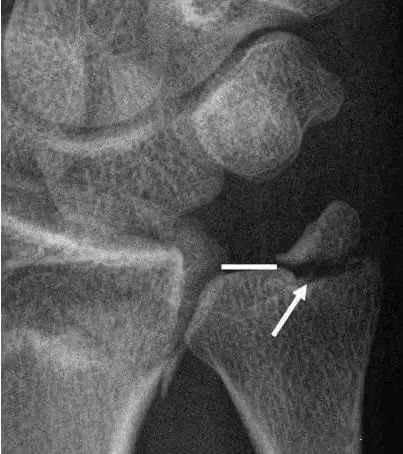

(8)肱骨内上髁骨折肘关节后脱位:两者均有肘部疼痛、肿胀,伸直位固定。但脱位为环击肿痛,弹性固定于135°、肘窝可扪及肱骨远端,鹰嘴上方空虚,肘部呈靴状畸形;X线片示脱位、无骨折征。关节向后内或后外脱位,肱骨内上髁骨折常可合并肘关节向后内或后外脱位。

肱骨内髁骨折:在小儿肱骨内髁内骨化中心未出现之前,X线上不能显示骨化中心位置。肱骨内髁骨折与内上髁骨折主要根据X线片上肱骨小头肱骨内上髁及桡骨小头骨化中心的位置变化加以鉴别。